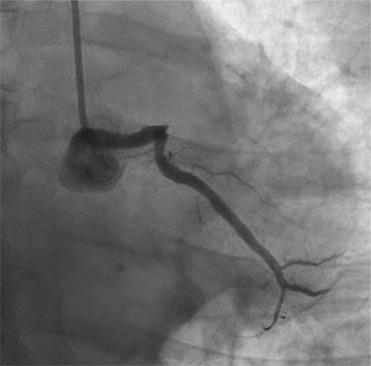

Infective endocarditis (IE) is a potentially life-threatening condition characterized by infection of the heart valves or endocardial surface, leading to significant morbidity and mortality. This case series explores four unusual presentations of IE, highlighting the diverse etiologies and complex multisystem complications that can arise from this condition. The clinical manifestations of IE can vary widely, ranging from systemic embolization to acute heart failure, reflecting the varied spectrum of pathogens involved and the patient's underlying health status. Key risk factors include preexisting valvular heart disease, intracardiac devices, intravenous drug use, and immunocompromised states. Prompt and accurate diagnosis is crucial for effective management, with echocardiography serving as the gold standard imaging modality and playing a key role as the first-line tool. Both transthoracic and transesophageal echocardiography are invaluable in identifying vegetations, evaluating valve function, and detecting potential complications such as abscesses, valve perforation, and intracardiac fistulas. The high sensitivity and specificity of echocardiography allow for early detection, even in cases with subtle or atypical presentations, ensuring that timely medical or surgical interventions are initiated. In addition, echocardiography is essential in monitoring treatment response, guiding clinical decisions, and determining the need for surgical valve replacement when severe damage or persistent infection is evident. This series emphasizes the importance of a multidisciplinary approach to treatment, which may include both medical and surgical interventions, tailored to the patient's specific clinical scenario. A heightened awareness of atypical presentations and the need for timely intervention are critical for improving patient outcomes, particularly in high-risk populations.